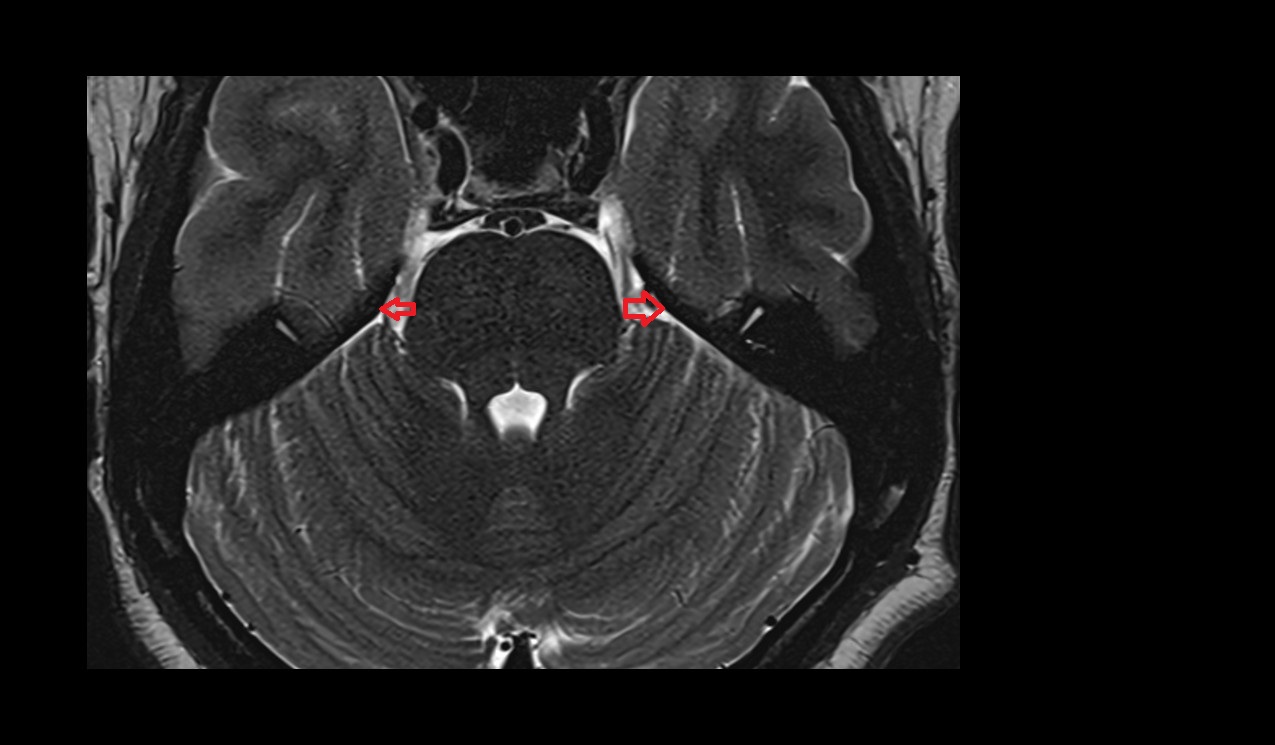

- Cerebellar tonsil (H IX)